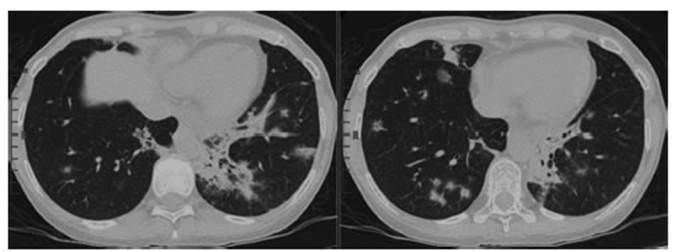

Chest CT (11/10/2021) (See

Figure 1):

The CT shows multiple peribronchovascular “ground glass” infiltrates with central

and peripheral distribution, with compromised patchy lungs predominantly bibasilar, and consolidations with air bronchogram

in left posterior basal segment.